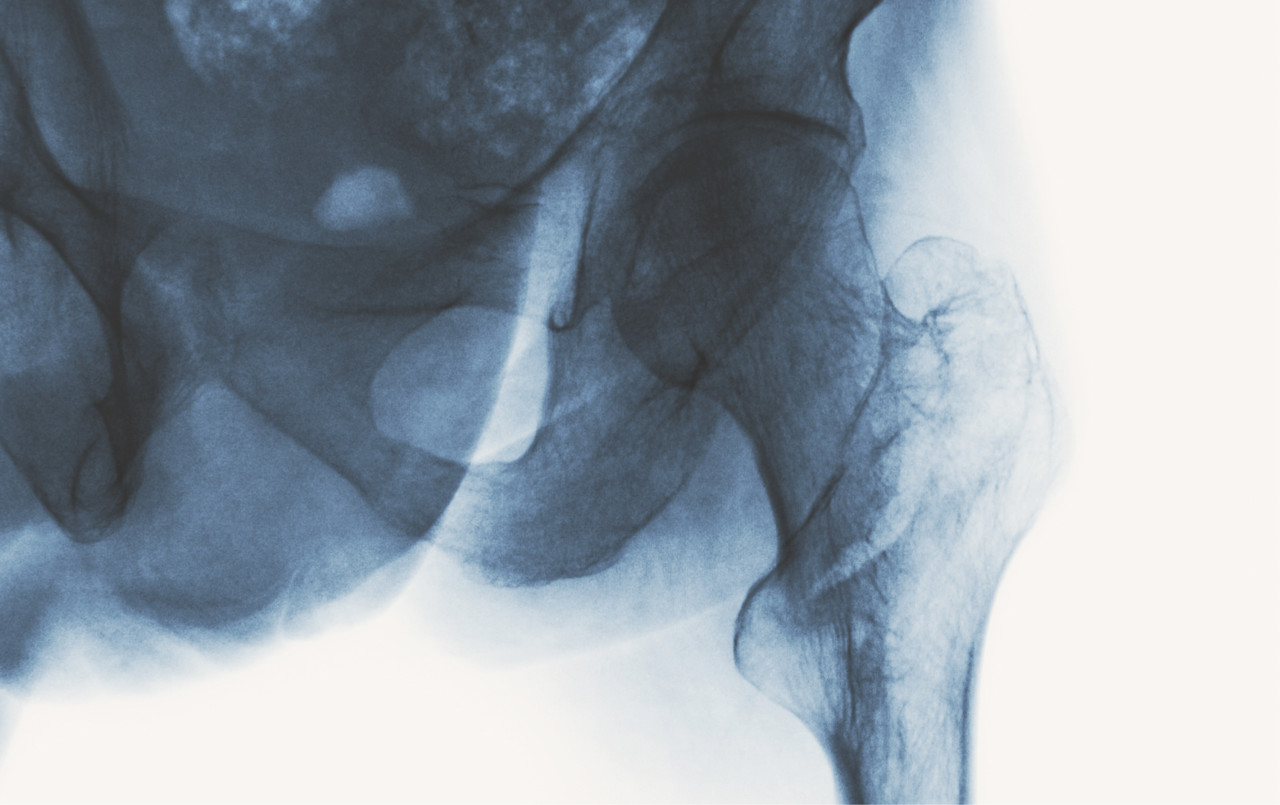

골다공증은 골밀도가 줄어들어 기침과 같은 작은 충격에도 골절이 쉽게 발생합니다. 특히 고관절 골절은 사망으로 이어질 수 있습니다

골다공증은 골밀도가 줄어들며 뼈가 다공성이 되어 약해지기 때문에 작은 충격에도 골절이 쉽게 발생합니다. 특히 고관절 골절은 사망 위험을 높이는 치명적인 결과를 초래할 수 있습니다.